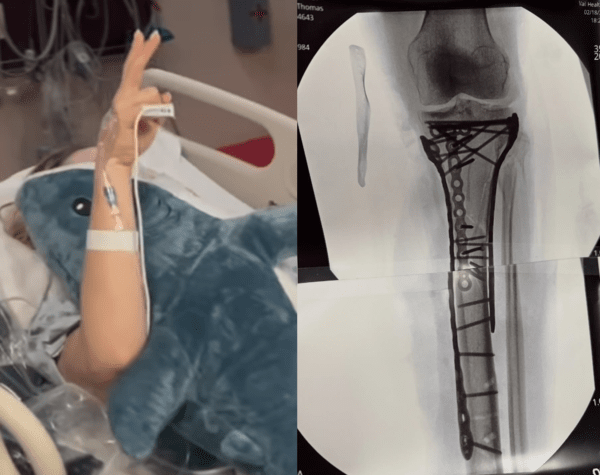

그녀는 21일 자신의 사회관계망서비스(SNS)를 통해 수술 후 근황을 전했는데, "수술은 무사히 끝났다"며 "완료하는 데 6시간이 조금 넘게 걸렸다"고 밝혔다.

이어 "뼈를 다시 맞추기 위해 많은 플레이트와 나사가 필요했다"며 "부상의 정도가 워낙 심하다 보니 수술 후 회복 과정이 쉽지 않았다"고 설명했다.

그럼에도 그녀는 쉽게 무너지지 않았다. 본은 "아직 퇴원하지는 못했지만 거의 다 왔다. 한 걸음씩 나아가고 있다"며 복귀를 향한 의지를 드러냈다.